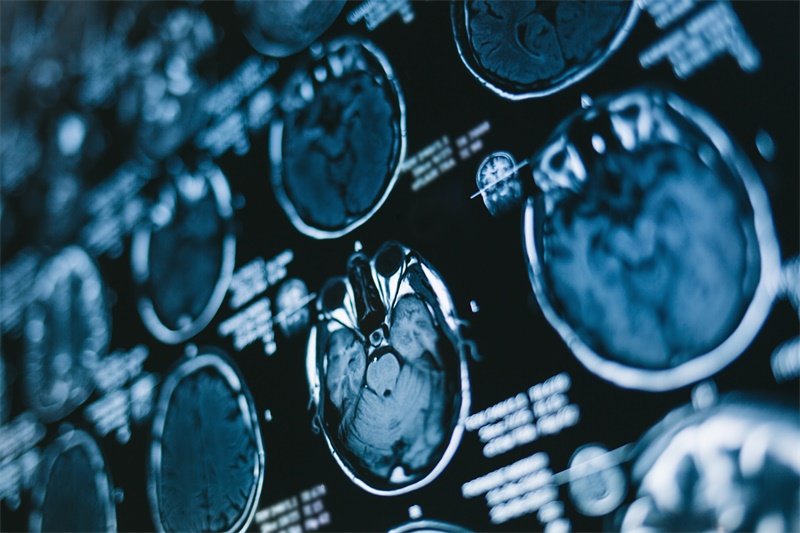

影像学检查是确诊侧脑室前角占位的金标准。通过CT或MRI检查,医生能够观察到脑室的形态变化、脑组织的结构损害及其周围的组织情况。影像数据能够为进一步的诊断和治疗方案提供重要参考。